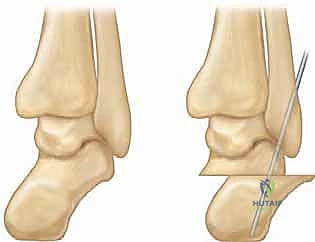

- تحرير اللفافة الأخمصية (Plantar Fascia Release - Steindler Stripping): يتم قطع اللفافة الأخمصية المشدودة في أسفل القدم لتقليل ارتفاع القوس.

- إطالة وتر أخيل (Achilles Tendon Lengthening): لتقليل الشد على مؤخرة القدم والسماح للكعب بالعودة إلى وضعه الطبيعي.